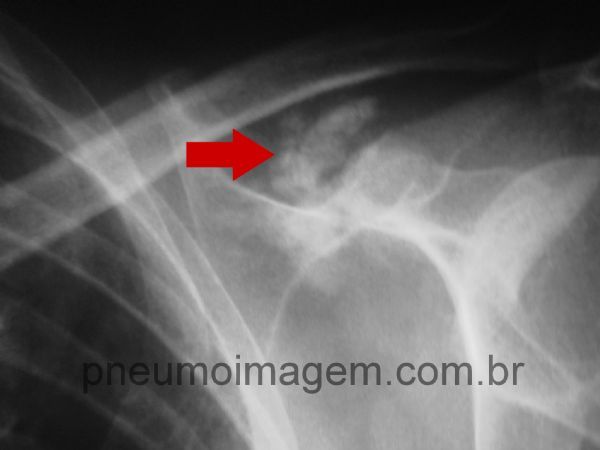

Observe a calcificação da cápsula articular em ombro esquerdo.

Calcificação da cápsula articular em ombro esquerdo.